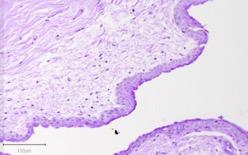

Images were taken using a Motic EasyScan slide scanner, and the goblet cells were counted in QuPath, a bioimage analysis program. A simple cell counting tool was used to manually quantify the goblet cells. Furthermore, the tissue was stained with Hematoxylin & Eosin to evaluate the thickness of the central cornea epithelium and to evaluate the cellular invasion (Figure 4). Richard-Allan Scientific Modified Mayer’s Hematoxylin was used to stain the nuclei, and Shandon Eosin Y was used as the counterstain. Both stains were distributed by Thermo Fisher Scientific. Images were taken using a Motic EasyScan slide scanner. The thickness was measured by quantifying all the stratified epithelial cells in the central cornea normalized to unit length, and all measurements were performed in QuPath. A cell detector was used in the appropriate region of interest – the central cornea – to quantify the number of stratified epithelial cells, and the length was measured using the polyline tool. Cellular invasion was measured by determining the length by which the cells invaded the epithelium, and the polyline tool was used to take this measurement.

Figure 4. H&E stain of central cornea in surgical (left) and chemical (right) models.